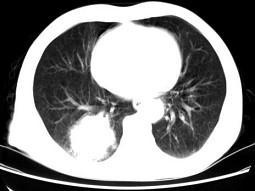

问题 男,66岁,胸痛一月,胸部CT如图,最可能的诊断是 ( )

选项 A、右下肺错构瘤 B、右侧炎性假瘤 C、右下肺动静脉瘘 D、右下肺肉瘤 E、右下肺周围型肺癌

答案 E